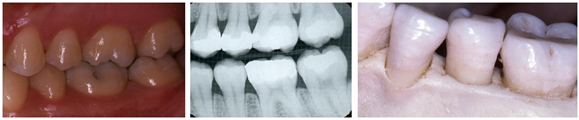

A dentist uses X-rays to see the nerve and blood vessels, the jawbone and between-the-teeth cavities. X-rays will not show whether or not the nerve and blood vessels are alive. But an abscess will eventually show up as bone loss around the bottom of the tooth’s root deep within the jaw bone. X-rays also show bone loss due to gum disease. Because it takes awhile to lose enough tooth structure or bone to be visible on an X-ray, between-the-teeth cavities and bone loss caused by an abscess or gum disease may not be evident for several months. A consequence of this time lag is a cavity, an abscess and/or gum disease are frequently much worse than indicated on an X-ray. And, because an X-ray is like a photograph it does not show the extent of a cavity or the loss of jaw bone from the cheek to tongue side. While X-rays are quite valuable, a dentist’s examination and experience are required to interpret them to determine an accurate diagnosis.